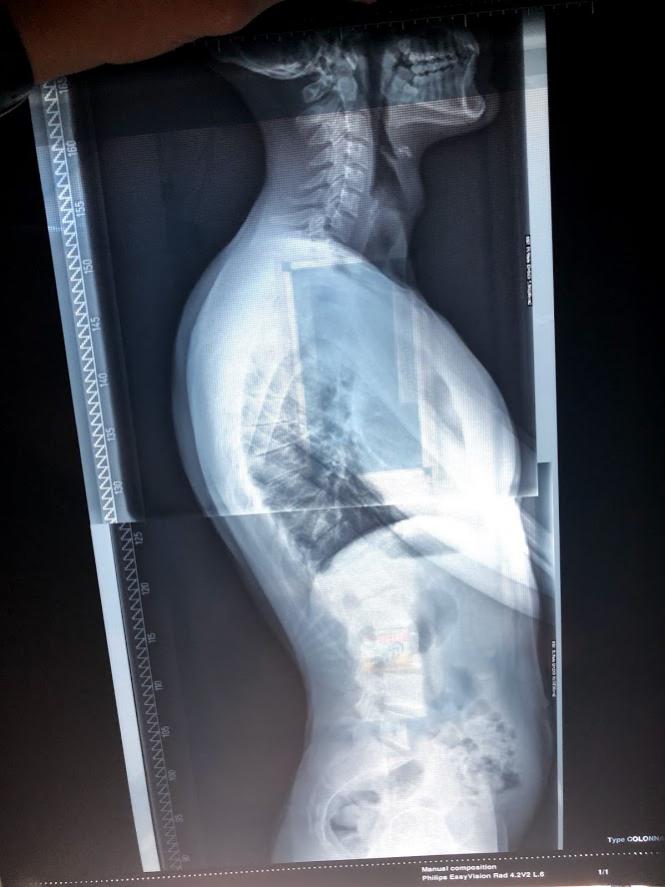

purtroppo trattasi di cifosi e lordosi ormai consolidate a livello osseo, giusto per farti una idea Clicca l'immagine per ingrandirla.

Te ne dico un paio, con l'ovvio beneficio di inventario legato alla mancanza di una visita dal vivo e alla semplice visione di un paio di foto ...

Hai 30 anni e non puoi modificare l'assetto osseo.

Chi ti racconta cose diverse lo fa per spillarti $.

Hai una cifosi "abbastanza normale"..nulla che pregiudichi un buon funzionamento articolare e nulla che comprometta la tua "estetica".

La zona lombare non mi sembra particolarmente iperlordotica...ma mi piacerebbe vedere meglio le proiezioni di L5 su L4 e su S1.

In sintesi...nulla di preoccupante (e nulla di modificabile).

Mangia bene ed allenati seriamente.

Forse così è più visibile